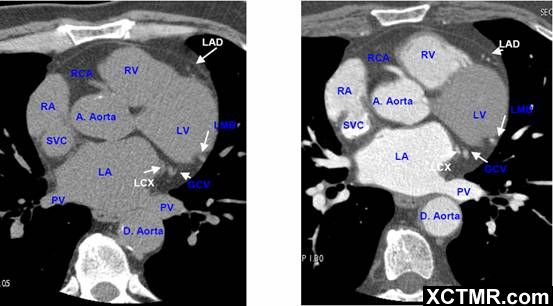

常用英文名称及缩写 LA - Left Atrium 左心房 RA - Right Atrium 右心房 LV - Left Ventricle 左心室 RV - Right Ventricle 右心室 Mitral Valve 二尖瓣 A. Aorta-Ascending Aorta 升主动脉 D. Aorta-Descending Aorta 降主动脉 SVC – Superior Vena Cava 上腔静脉 IVC – Inferior Vena Cava 下腔静脉 PA - Pulmonary Artery 肺动脉 PV - Pulmonary Vein 肺静脉 LMA - Left Main Artery 冠状动脉左主干 LAD - Left Anterior Descending Artery 左前降支 LCX - Left Circumflex Artery 左回旋支 LMB - Left Obtuse Marginal Branch 左边缘支(钝缘支) RCA - Right Coronary Artery 右冠状动脉 PDA - Posterior Descending Artery 后降支 Conus Branch 右动脉圆锥支 LAA – Left Atrial Appendage 左心耳 RAA – Right Atrial Appendage 右心耳 CS - Coronary Sinus 冠状窦 MCV – Middle Cardiac Vein 心中静脉 GCV –Great Cardiac Vein 心大静脉 PIVV – Posterior Intraventricular Vein 后室间静脉(心中静脉) PLVV – Posterior Left Ventricular Vein 左室后静脉 PLV – Posterior Lateral Vein 左室后侧静脉(边缘静脉) | |